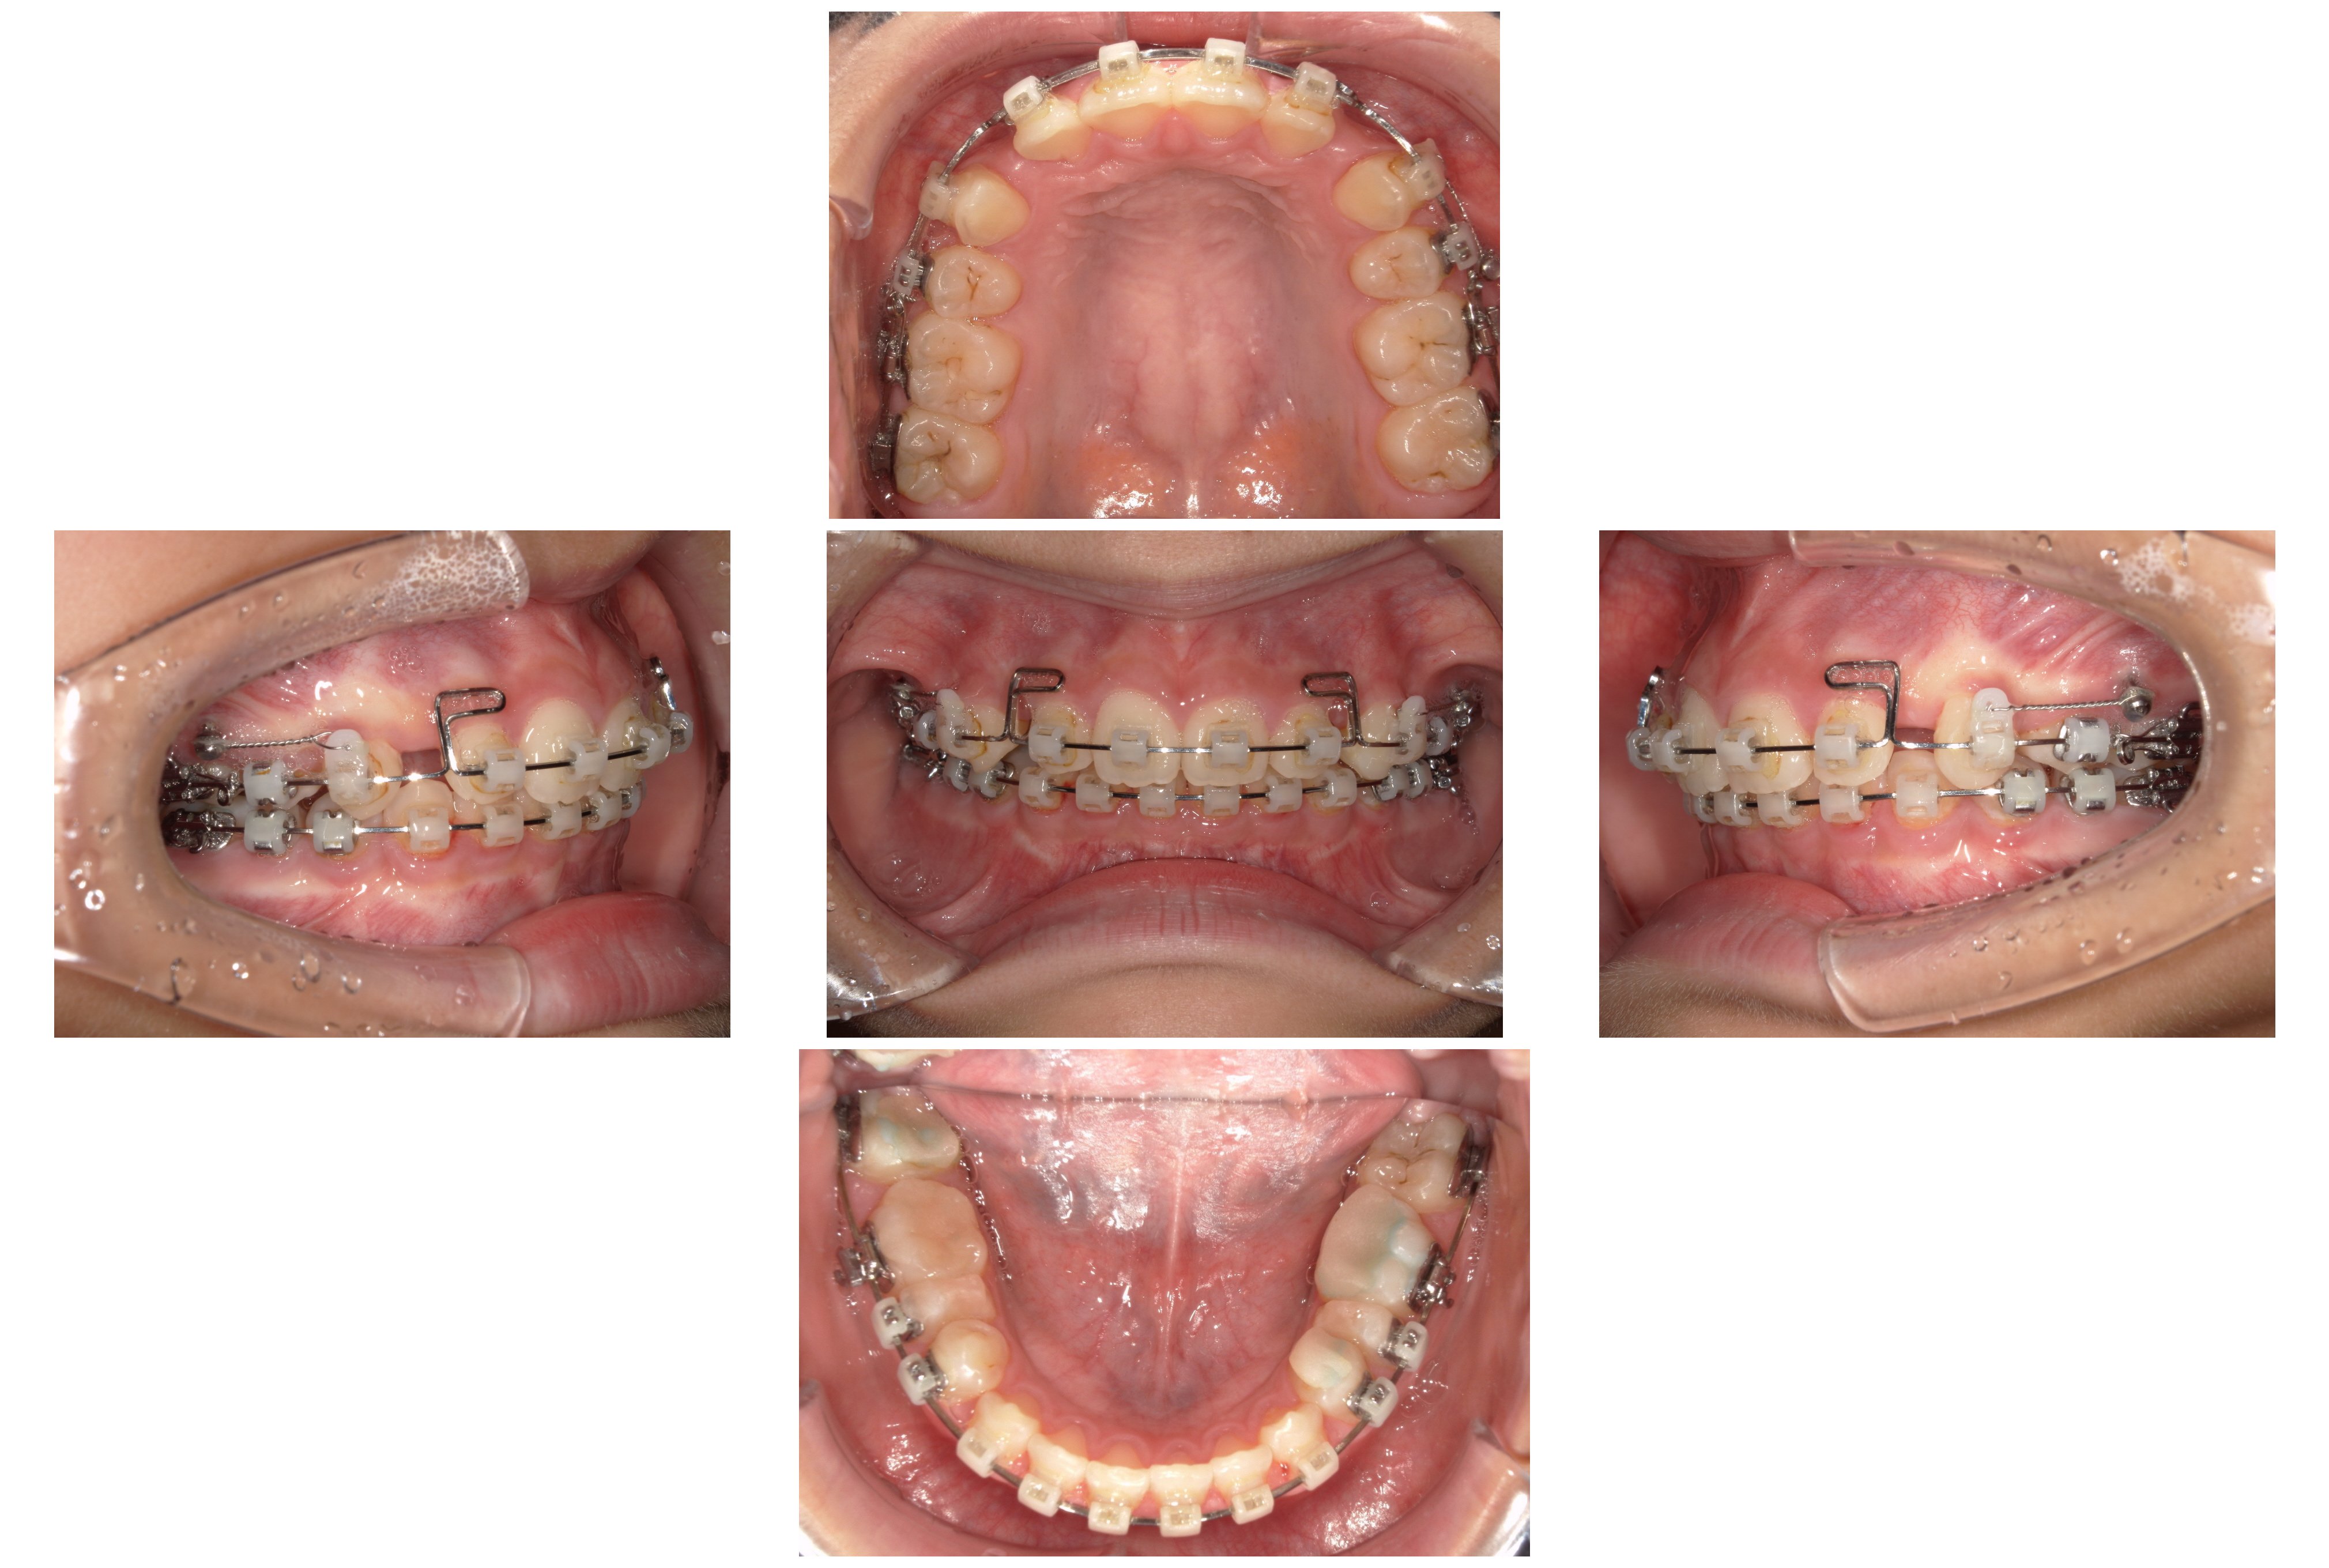

▼2023年1月

①装置装着~4か月後:咬み合わせの土台作り

まずは犬歯を後ろへ移動させるとともに、深い咬み合わせ(過蓋咬合)を改善するため、下顎にワイヤーを2本用いる手法で、前歯を押し下げて咬み合わせを浅くすることで咬合挙上(こうごうきょじょう)を図りました。